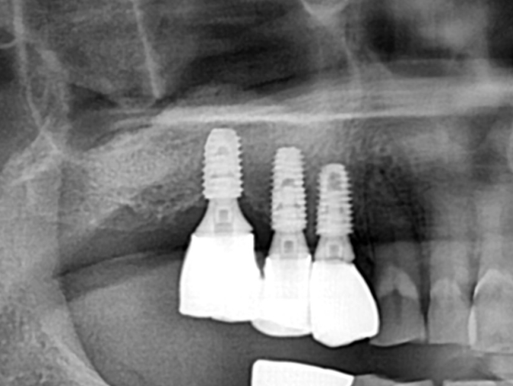

After

위 케이스에서는 상악동 거상술을 측방 접근법으로 시행하여 뼈 이식을 충분히 시행한 뒤 임플란트를

식립하여 단단한 골 지지를 얻을 수 있도록 하였습니다.